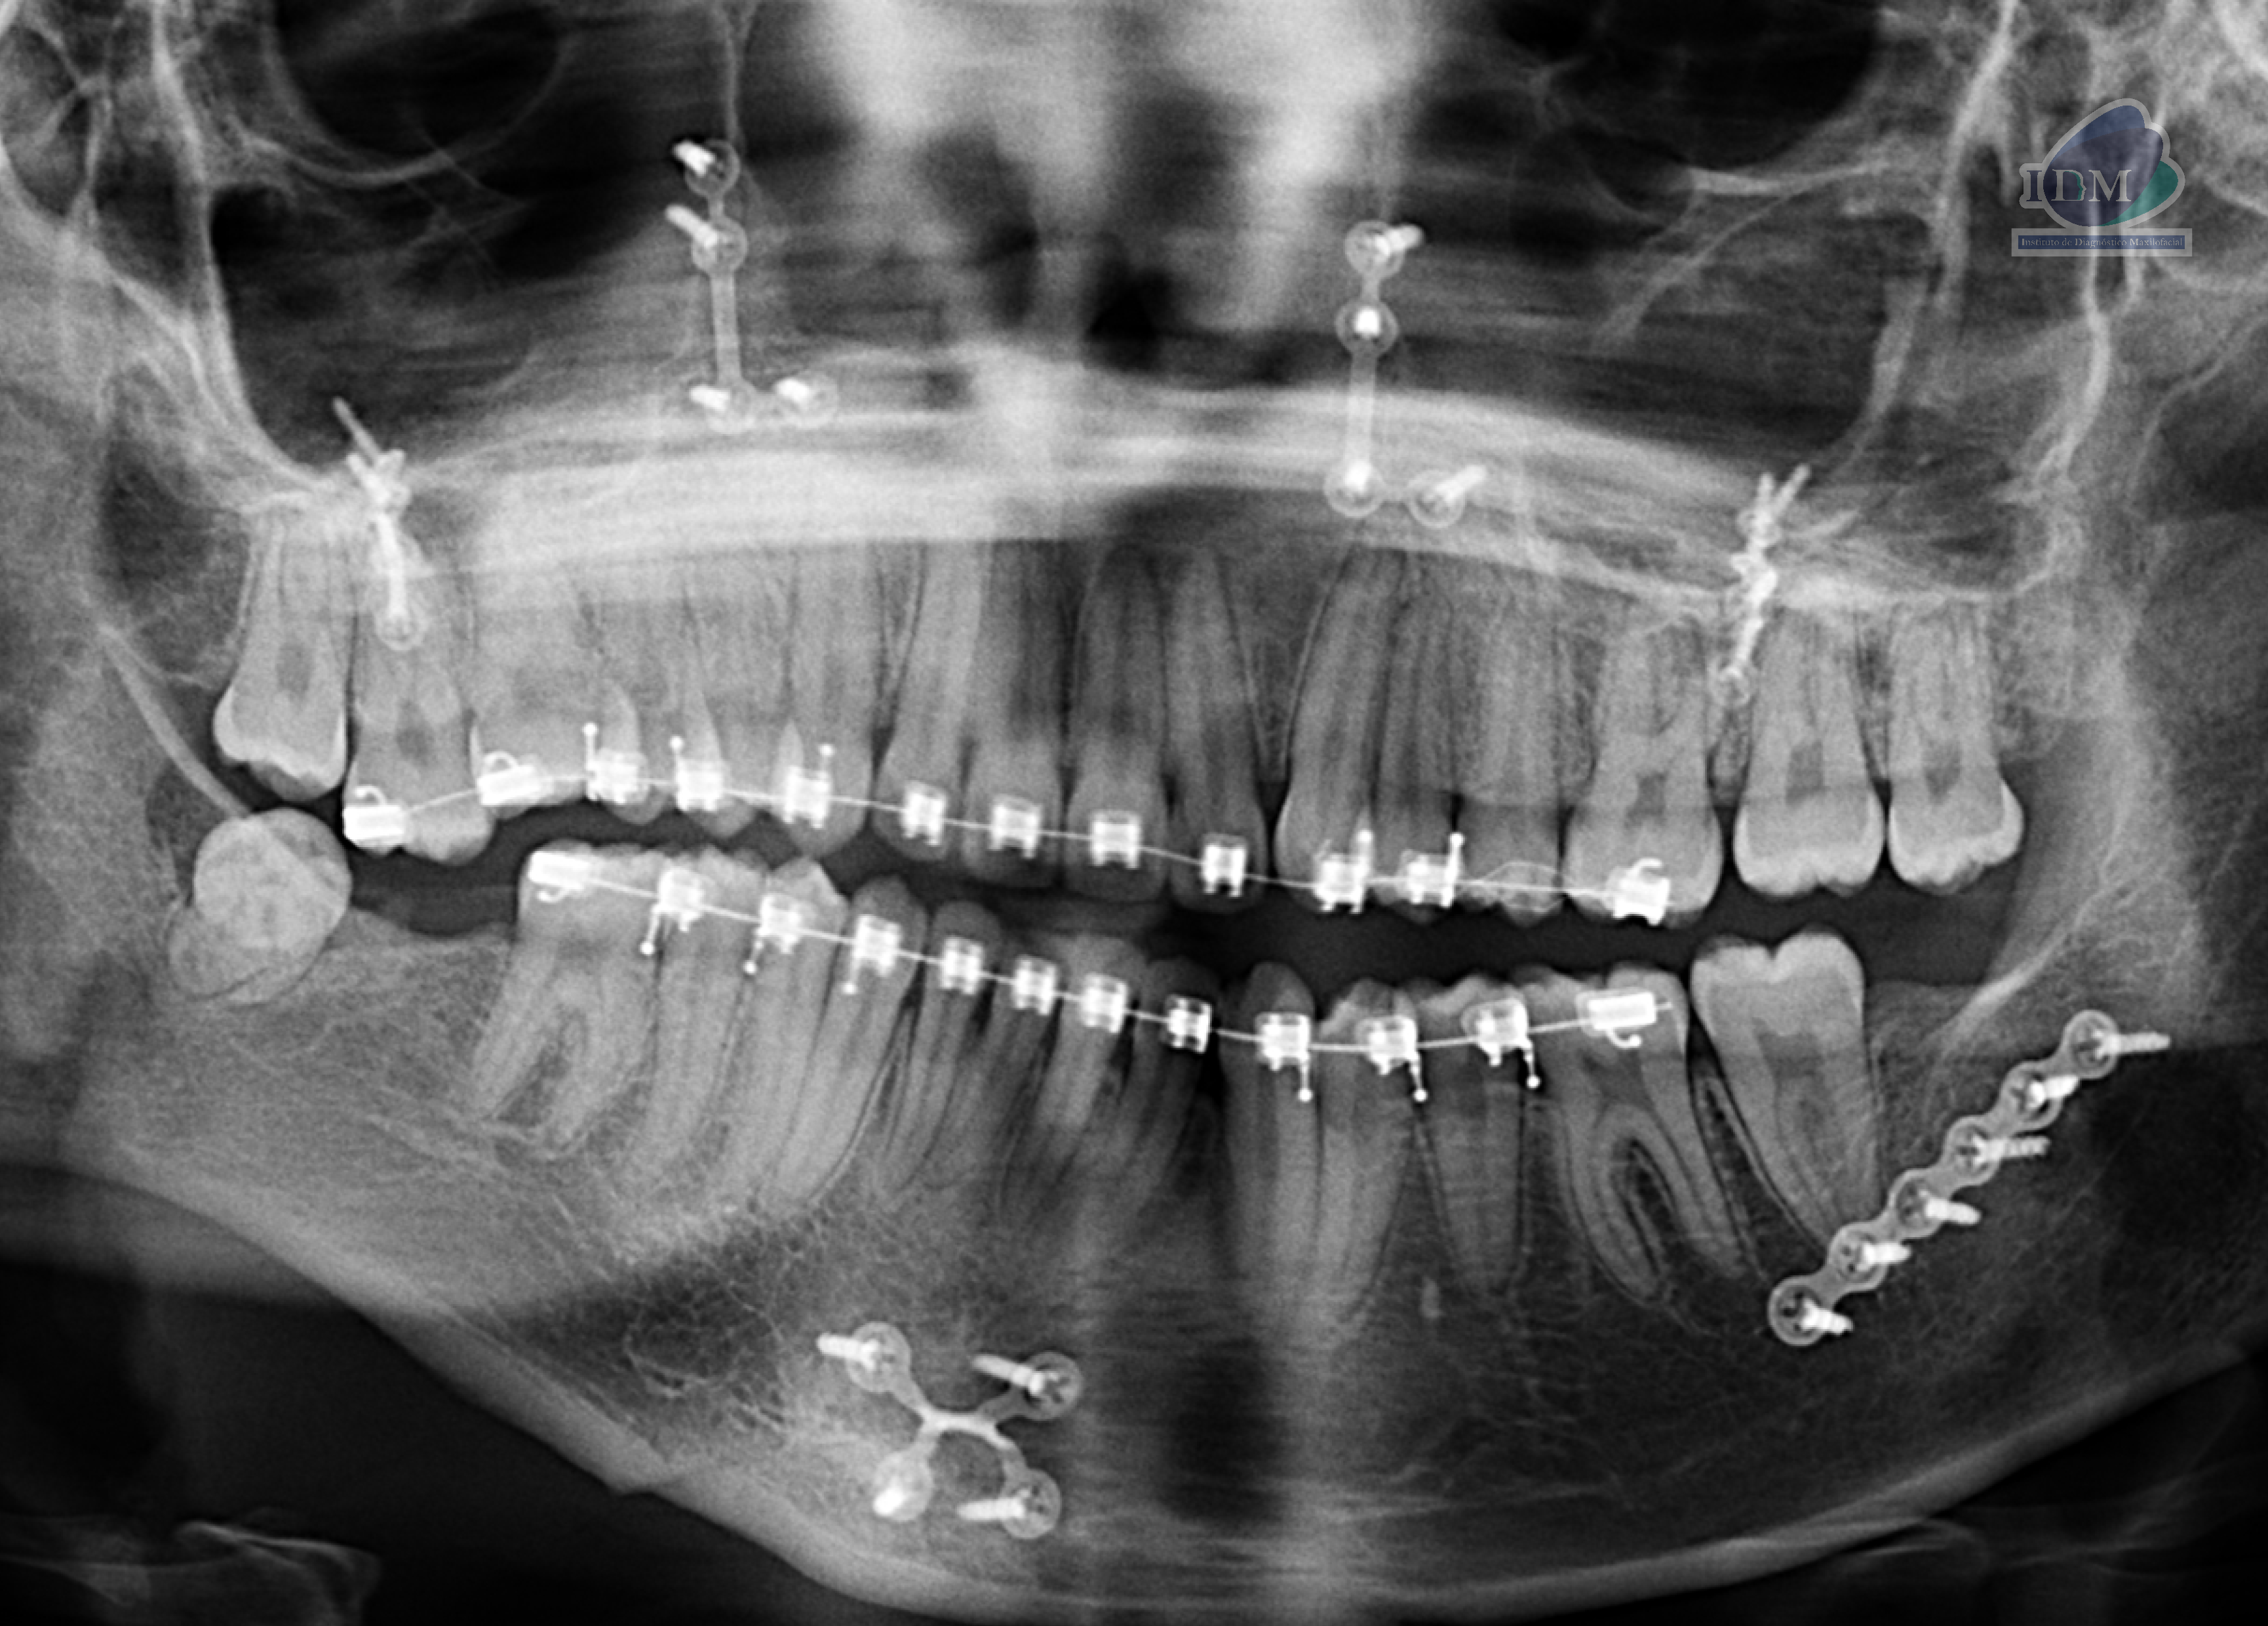

Radiografia Panorámica

A la evaluación de la radiografía panorámica se evidencia múltiples placas con tornillos de fijación bimaxilar así como aparatología de ortodoncia bimaxilar.

Evidenciando una alteración de la morfología de rama mandibular derecha.